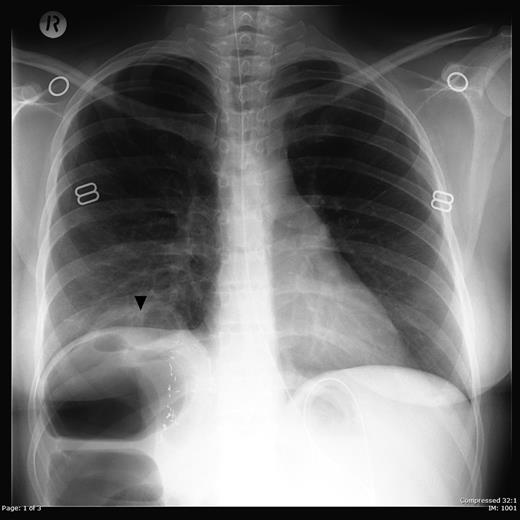

The patient's symptoms resolved postoperatively and mother and baby discharged home on the seventh postoperative day. Retrospective review of the preoperative erect chest X-ray showed a knuckle of herniated colon was in fact visible above the diaphragm (Figure 3).

Erect chest radiograph showing a loop of bowel (arrowhead) projecting above the right hemidiaphragm. Clips are seen in the right upper quadrant consistent with previous liver surgery.